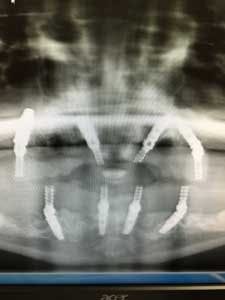

A panoramic radiograph (figure 8) and cone beam CT (CBCT) scan were obtained for evaluation of alveolar bone height and width and all sinus and mental foramen positions.

In the maxilla and mandible, distal implants were placed at proper 30- to 45-degree angles, avoiding sinus perforation and trauma to the mental foramen, respectively.

Anterior implants were placed straight, with the exception of the maxillary left implant placed to avoid a previously developed periodontal defect. All implants were grafted with a combination of mineralized and demineralized human bone allografts, and remaining sockets bone-grafted to enhance alveolar ridge preservation (figure 10). (2)

Transmucosal abutments or multiunit abutments were then placed onto dental implants, using straight, 17-degree, or 30-degree angulation to conform to the conversion prosthesis for proper stability and torquing.

Provisional prostheses were then positioned and upon proper stability, function, and cosmetic appearance were torqued to 15 Ncm. At this point, the occlusion was evaluated; posterior occlusion was adjusted to be extremely light, and occlusion associated in the anterior region carried more inter-arch load (figure 11). (2)